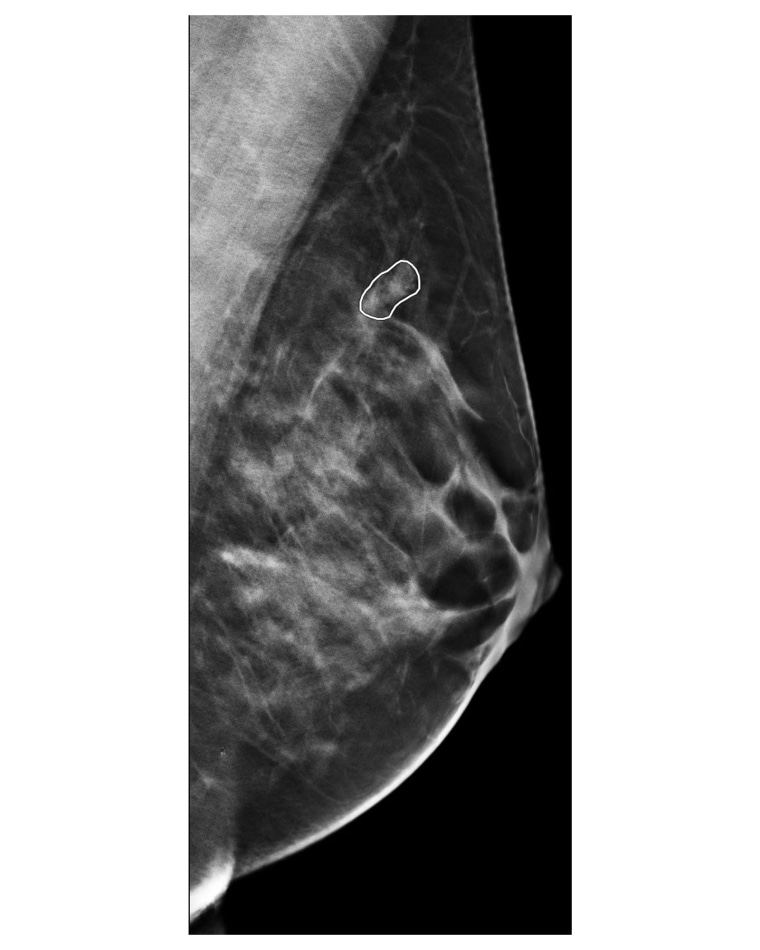

Os médicos deram uma segunda olhada por um motivo: Programas de inteligência artificial Desenha um círculo ao redor do seio esquerdo que parece suspeito.

Como o software de IA colocou essa bandeira vermelha, Hall, 55, recebeu um pedido de ultrassom que resultou em uma biópsia. Havia quatro tumores cancerígenos na área detectada pela IA.

“Isso teria sido completamente perdido sem a IA”, disse o Dr. Shawn Raz, diretor médico e diretor de inovação da SimonMed Imaging em Tempe, Arizona, onde Hall fez sua mamografia.

Não só o tecido mamário de Hall era denso, mas as camadas de tecido se cruzavam umas sobre as outras em um padrão particularmente complexo.

“Isso camuflou o câncer”, diz Raj, especialista em imagens de mama. “Até eu poderia ter perdido.”